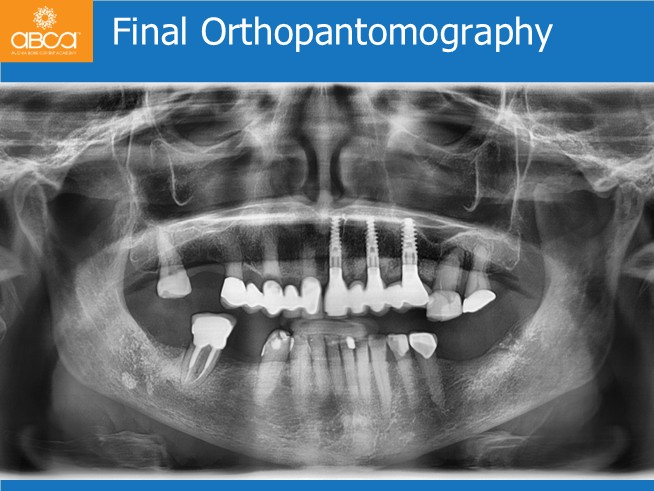

Treatment plan includes extraction of the teeth and roots from #21 (9) to #25 (13). Without opening a flap, placement of 3 immediate implants for an immediate bridge with 5 teeth. Placement of the final Nobel Procera bridge 6 months post-op.